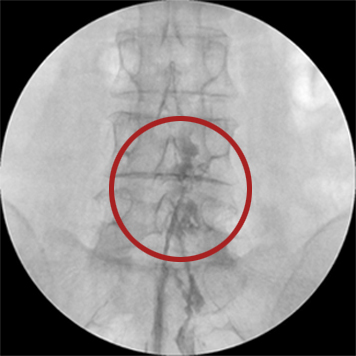

신경성형술

2mm의 초소형 카테터를 삽입하여 통증의 원인이 되는 부위를 찾아 신경 유착을 풀어주는 시술로 가장 대중적으로 사용되고 있는 척추질환 비수술치료입니다.

□ 이동식 X-ray(C-arm X-ray)로 진행 모습을 실시간으로 확인하여 안전